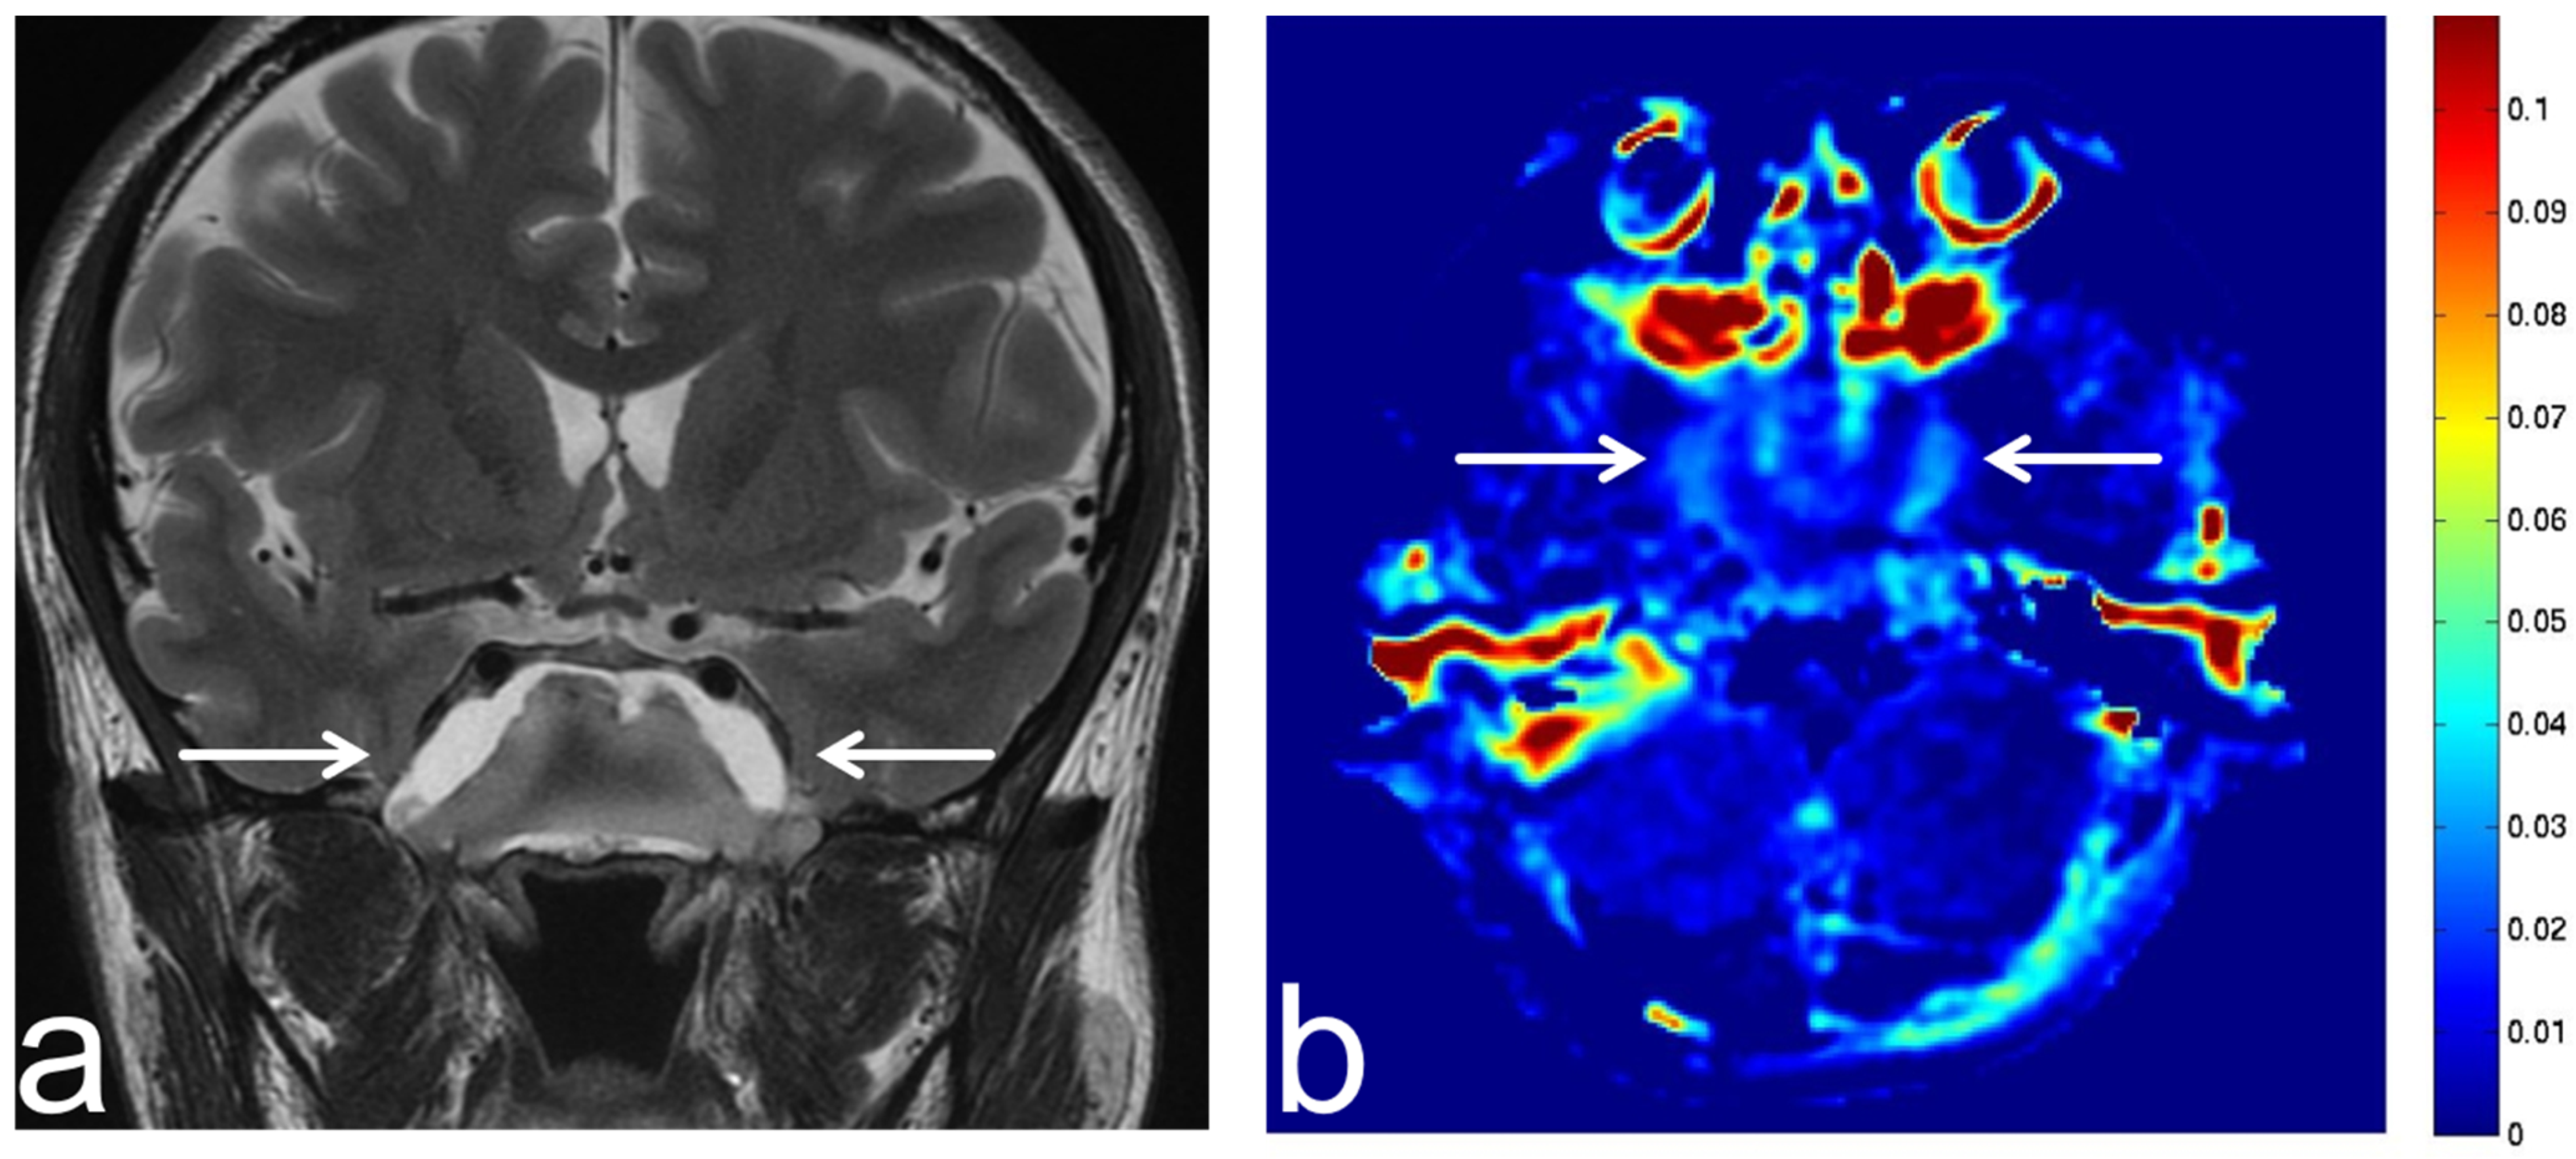

8.5. Hippocampal Sclerosis